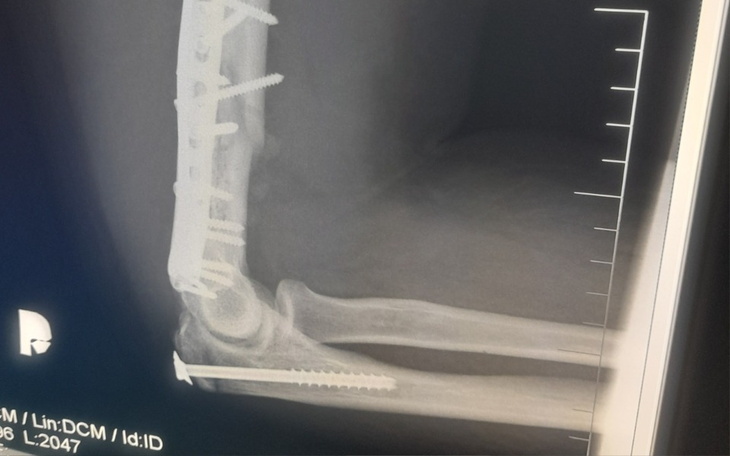

Kość zespolono blachami, śrubami oraz gwoździem. Złamania były na tyle skomplikowane, że do ich zespolenia celem zrośnięcia potrzebne były kawałki mojej kości wycięte z talerza biodrowego miednicy.